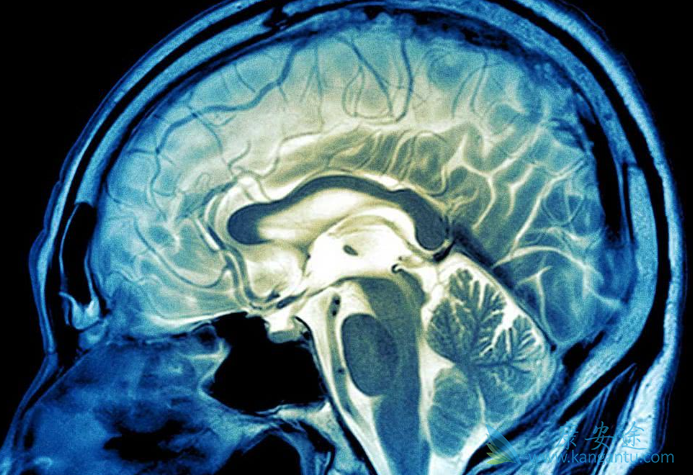

什么是脑瘤?脑瘤的症状有哪些?脑瘤是颅内肿瘤的简称,和其它肿瘤一样,也有良性和恶性之分。通常人们所说的“脑癌”,泛指大脑恶性肿瘤,比较常见的就是脑胶质瘤。脑瘤会造成神经系统的功能障碍,严重时会危机生命,所以脏我脑瘤的症状有助于尽早发现病情,尽早开始治疗。

脑瘤的症状:1)起病方式。常较缓慢,病程可自1~2个月至数年不等。有些病例可呈急性或亚急性发病,甚至可能出现卒中。后者多数是因肿瘤的恶性程度较高,进展迅速,或因肿瘤发生出血、坏死、囊变等继发性变化的结果。2)颅内压增高症状包括“三主征”,即头痛、呕吐及视盘水肿。

3)脑瘤的局灶性症状。主要包括肢体的乏力、瘫痪及麻木,抽搐或癫痫发作,视力障碍、视野缺损,嗅觉障碍,神经性耳聋,语言障碍,平衡失调,智能衰退,精神症状及内分泌失调、发育异常等。这些症状的出现往往是由脑瘤所在的部位决定,不同部位的脑瘤对应的症状也有所不同。